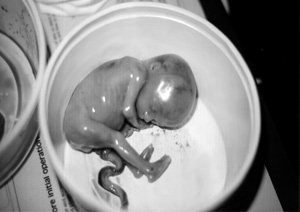

Εικόνα 7: Τροφοβλαστική διήθηση στο ενδοτραχηλικό στρώμα (χρώση πανκερατίνης). Εικόνα 8: Έμβρυο 20 εβδομάδων.

Διήθηση του ενδοτραχηλικού στρώματος από τροφοβλαστικά στοιχεία (εικ. 7). Αρρεν κύημα 20 εβδομάδων βάρους 192 γρ, αντιστοιχών σωματομετρικά χωρίς εμφανείς συγγενείς διαμαρτίες της διάπλασης (εικ. 8).